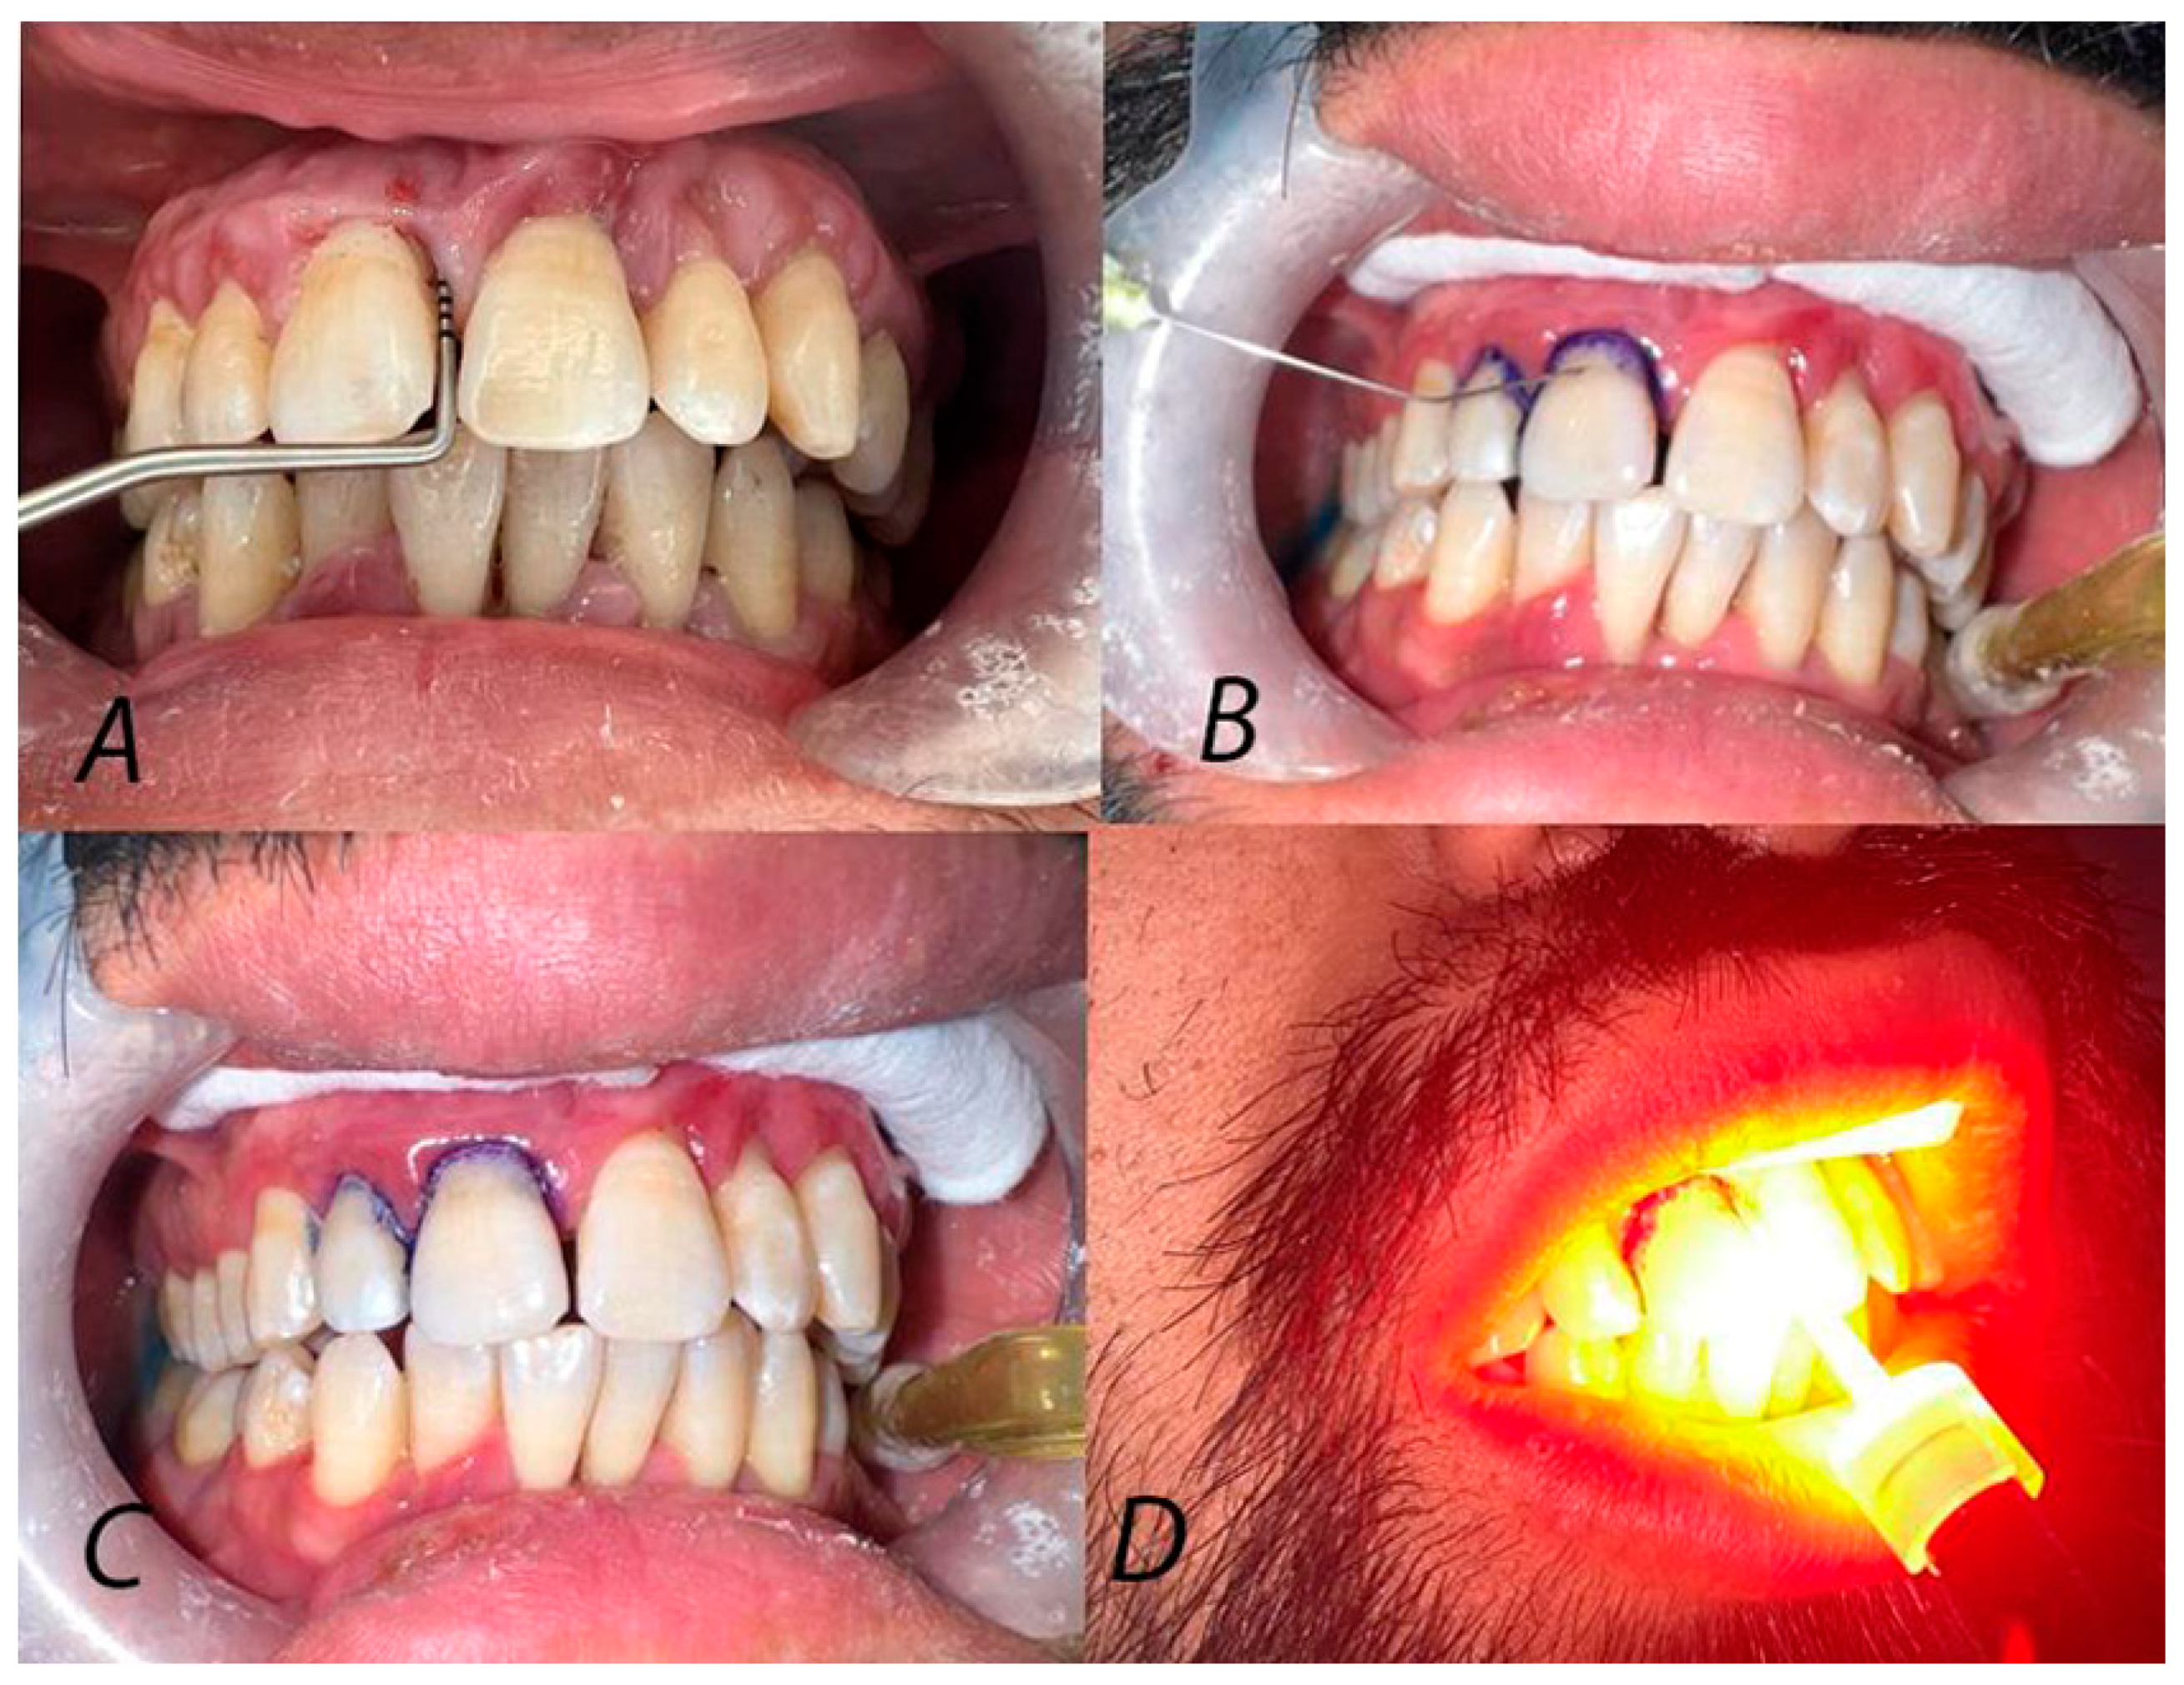

2.5. Randomization and Treatment Protocol